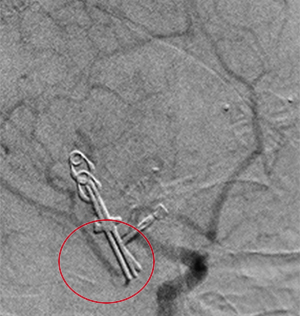

コイル塞栓手術前

コイル塞栓手術後